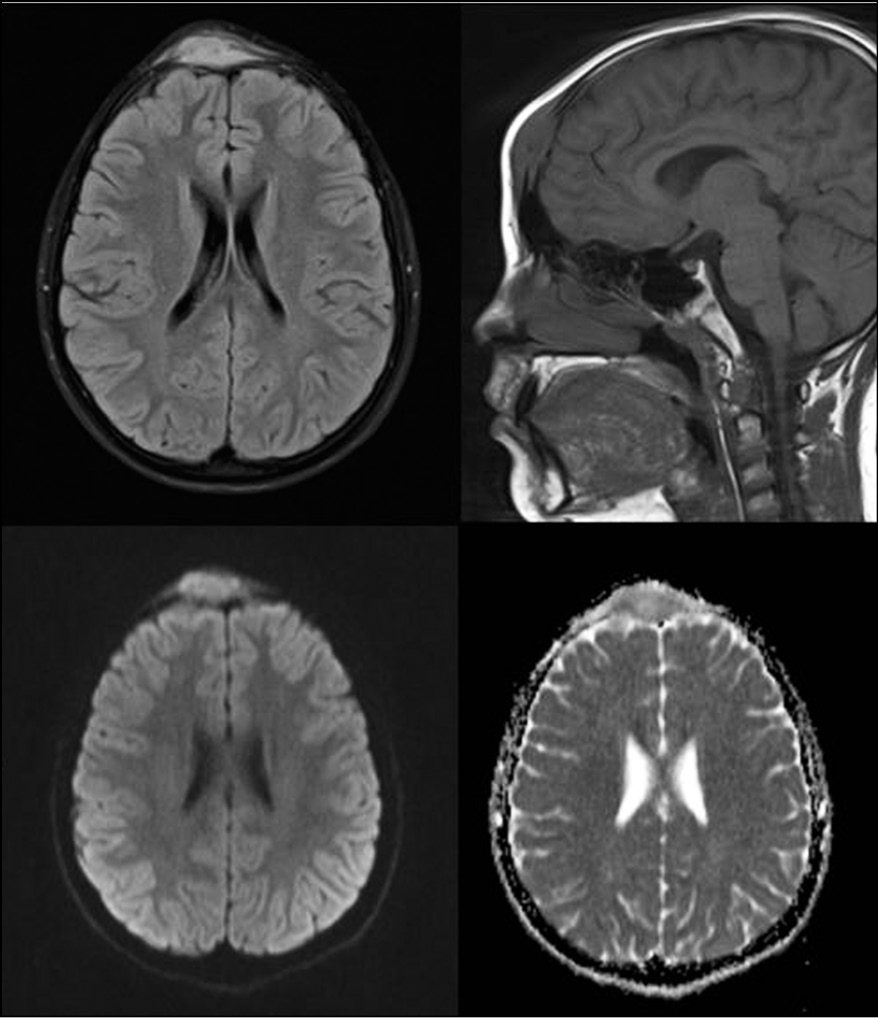

According to the brain MRI data, a subcutaneously located space-occupying lesion was detected in the frontal region parasagittally, with a mild right-sided priority, with a non-uniformly increased MR signal in the T2-WI and T2-dark fluid modes, with signs of diffusion restriction, of an ovoid shape with indistinct uneven boundaries, sized 47 × 17 × 35 mm. It was widely adjacent to the squama of the frontal bone, with destruction of the external and internal cortical plates with a minimal intracranial soft tissue component, limited by the brain dura mater (Fig. 5).

Fig. 5. Magnetic resonance imaging of the head. Top row from left to right: T2-TIRM, T1-WI; bottom row from left to right: diffusion-weighted image (B-factor 800 mm2/s), measured diffusion coefficient. Subcutaneous space-occupying lesion of increased signal in T2-TIRM, isointense in T1-WI, with signs of diffusion restriction.

The most common finding based on MRI data is a mild diffuse decrease in the signal according to the T1-WI data, combined with an increase in the signal according to the T2-WI. Edema is also visible in the soft tissues surrounding the lesion, as shown by an increased signal on the spin-echo inversion-recovery sequence. The focus of eosinophilic granuloma of the skull bones limits diffusion compared with the white matter of the brain [6]. The described changes are not specific and can occur in a number of conditions, including osteomyelitis, traumatic changes, and avascular necrosis [7].